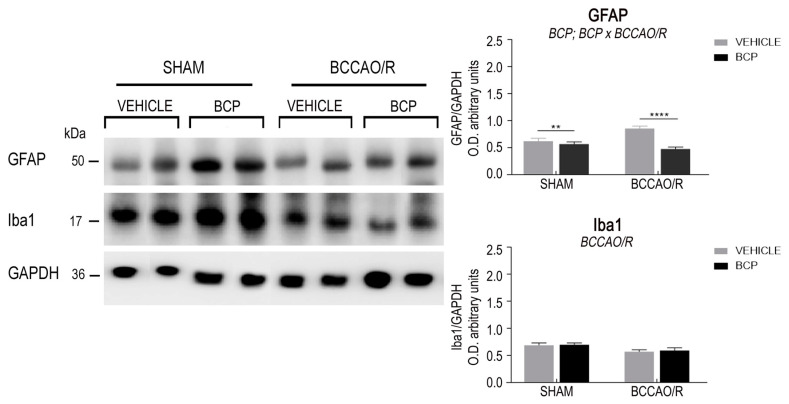

The effects of the BCCAO/R without and with preventive administration of BCP on the relative levels of TRPV1, BDNF, trkB, GFAP, and Iba1 proteins are summarized in Table 1 and shown in Figure 1 and Figure 2. Statistical analysis of O.D. values of the immunostained protein bands performed by two-way ANOVA (main factors BCCAO/R and BCP) (Table 1) revealed that both the BCCAO/R-induced molecular changes and the effect of the BCP pre-treatment occurred in the frontal cortex, whereas no statistically significant differences were evident in the temporal-occipital cortex.

2.1.4. The GFAP Protein Levels

The antibody against GFAP, as expected [ref. 59], recognized a protein band with a relative mw of about 50 kDa (Figure 2). Assessment of the GFAP densitometric values by a two-way ANOVA (Table 1) revealed an effect of BCP treatment (p < 0.0001) and a BCP × BCCAO/R interaction (p = 0.0006). Further post-hoc tests showed that, in vehicle-treated animals, the GFAP protein relative levels increased by 27% in BCCAO/R rats as compared to sham-operated ones (p = 0.0015). In BCCAO/R rats the GFAP relative levels decreased by 44% in BCP-treated compared to vehicle-treated rats (p < 0.0001).

2.1.5. The Iba1 Protein Levels

The antibody against Iba1 labeled a protein band with a relative mw of about 17 kDa (Figure 2), according to the expected mw of the protein [ref. 60]. Assessment of the Iba1 densitometric values by a two-way ANOVA (Table 1) revealed an effect of BCCAO/R (p < 0.0007).